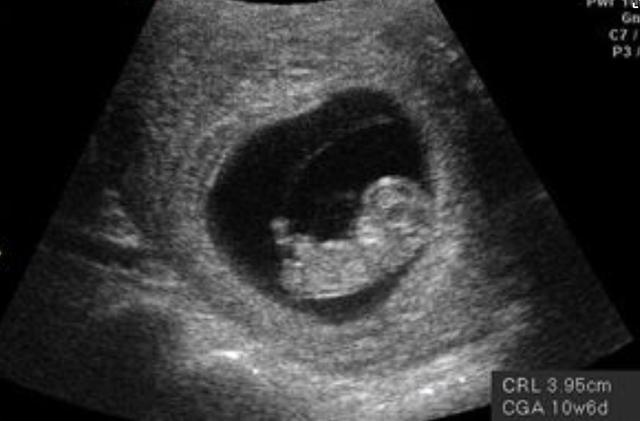

在前3个月时,尽管胎儿在妈妈的肚子里动来动去,但是孕妇一般是感觉不到的。到了3个月之后,孕妇的身材会有些明显变化了,肚子能看到隆起的样子了,因为这时候胎儿已经长大了。通常,3个月大的胎儿为15g左右,身长就是10cm左右,如小手掌般大,所以,这时候的孕肚还不会给孕妇的生活带来很大的影响。